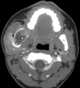

Unerupted tooth

Dentigerous cyst, also known as follicular cyst is an epithelial-lined developmental cyst formed by accumulation of fluid between the reduced enamel epithelium and crown of an unerupted tooth. It is formed when there is an alteration in the reduced enamel epithelium and encloses the crown of an unerupted tooth at the cemento-enamel junction. [Source: Wikipedia ]